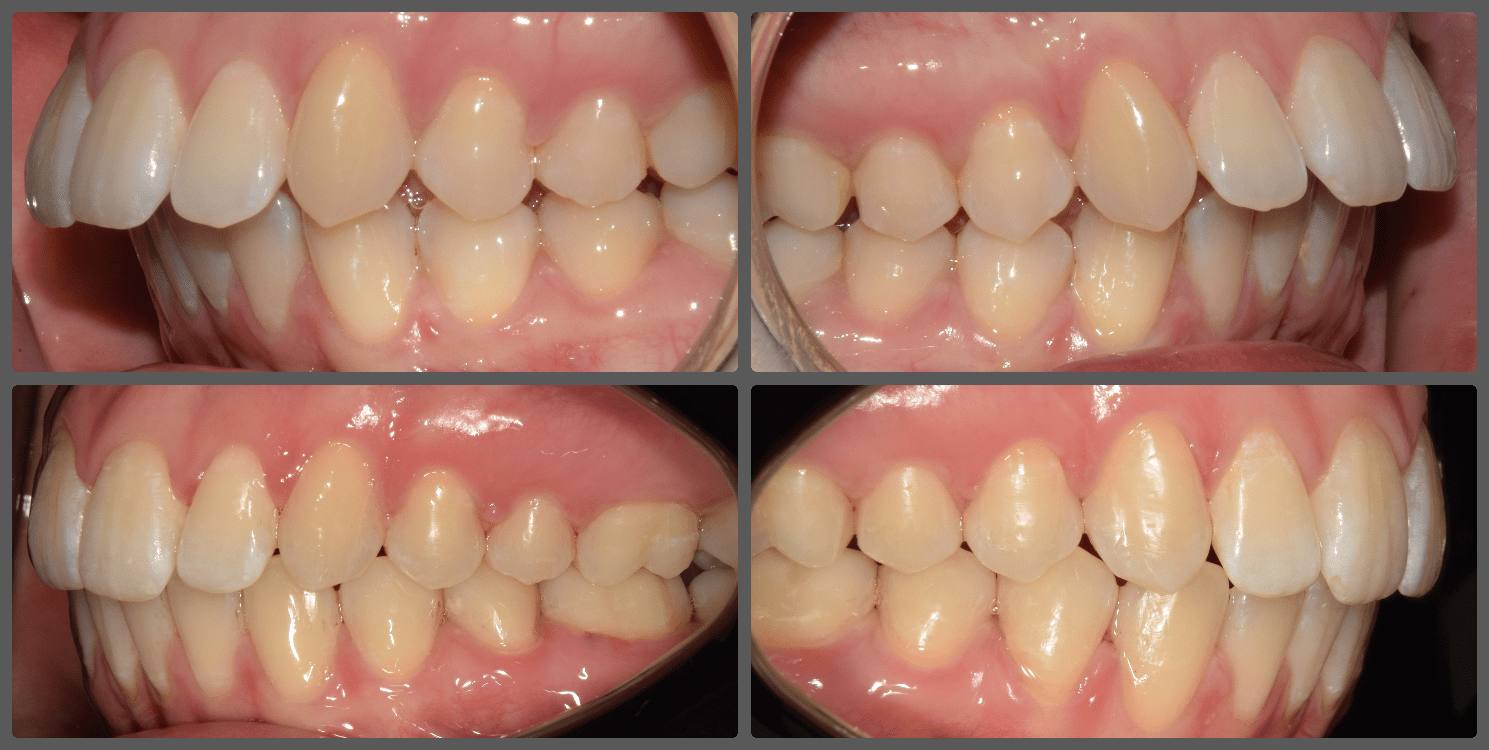

Bálint a 90 fokban elfordult jobb felső kismetszője miatt keresett meg engem. A vizsgálatokat követően kiderült, hogy a probléma ennél jóval komplexebb: súlyos keresztharapást, súlyos mélyharapást és felső rágósík billenést diagnosztizáltam nála. Alsó-felső H4 önligírozó fogszabályozó készülék, intermaxilláris gumihúzás és elülső harapásemelők segítségével korrigáltuk az eltéréseket. A bal oldali rágósík billenést fogszabályzási miniimplantátum alkalmazásával oldottuk meg. A bal felső-elülső fogakat felfelé mozgattuk, a miniimplantátumhoz húzva. Bálint esete igen komplex volt, ám kiváló együttműködésének köszönhetően 26 hónap alatt végeztünk a kezelésével (beleértve a 2-3 hónapos COVID-19 miatti leállást is). Az eredmény úgy gondolom magáért beszél!